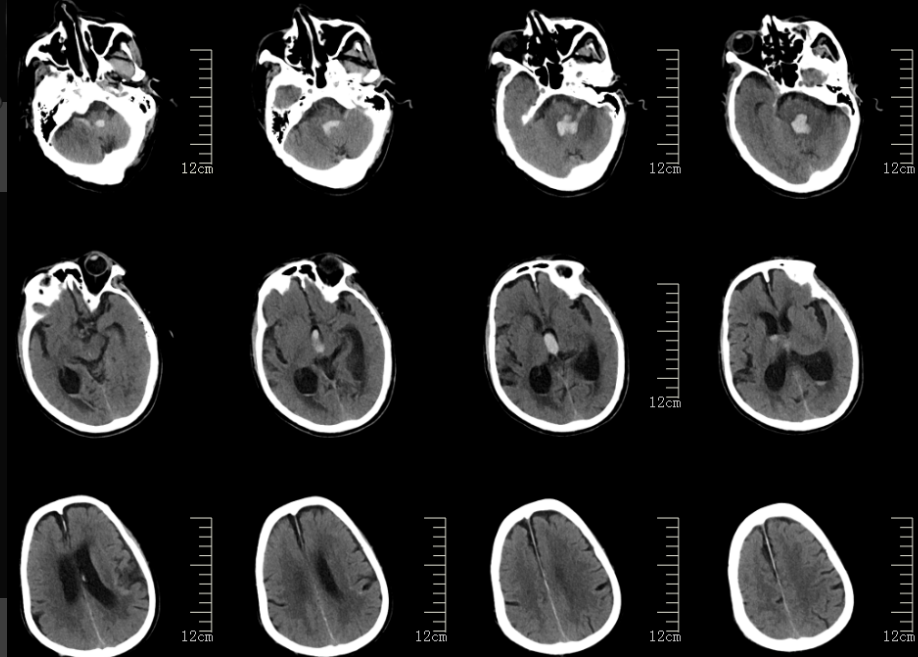

2024年12月22日中午,84岁的罗大爷刚与家人吃完饭,突然出现肢体活动障碍,随后意识也出现障碍。家属立即呼叫120,将其送往阆中市人民医院。急诊进行头颅 CT检查,结果显示脑干出血并破入脑室,伴有梗阻性脑积水。患者随即通过绿色抢救通道被送入神经外科。值班医生杨学明副主任医师接诊后发现,患者脑干部位积血量并不多,无需进行手术治疗,但破入脑室的积血却引发了致命问题——阻塞了脑脊液的循环通路。脑室内每天会产生350-550ml的脑脊液,正常情况下,脑脊液会沿着自身的循环通路被吸收,而循环通路一旦堵塞,意味着每天产生的脑脊液会积聚在脑子里,娇嫩的脑组织根本容纳不下这么多液体。

针对这一情况,神经外科李想主任立即组织手术组医师开展病情讨论,并制定了具体治疗方案:立即施行三脑室底造瘘+侧脑室置管外引流术。在麻醉科团队的全力配合下,手术由杨学明副主任医师与张珩副主任医师联合主刀,不到 2小时便顺利完成。术后复查CT显示,患者的脑积水症状已消失,脑室原有的积血也已完全吸收不见。术后5天,顺利拔除侧脑室引流管;19天后,患者顺利出院进行康复锻炼,随访至今未再出现脑积水。

术前影像

术后影像